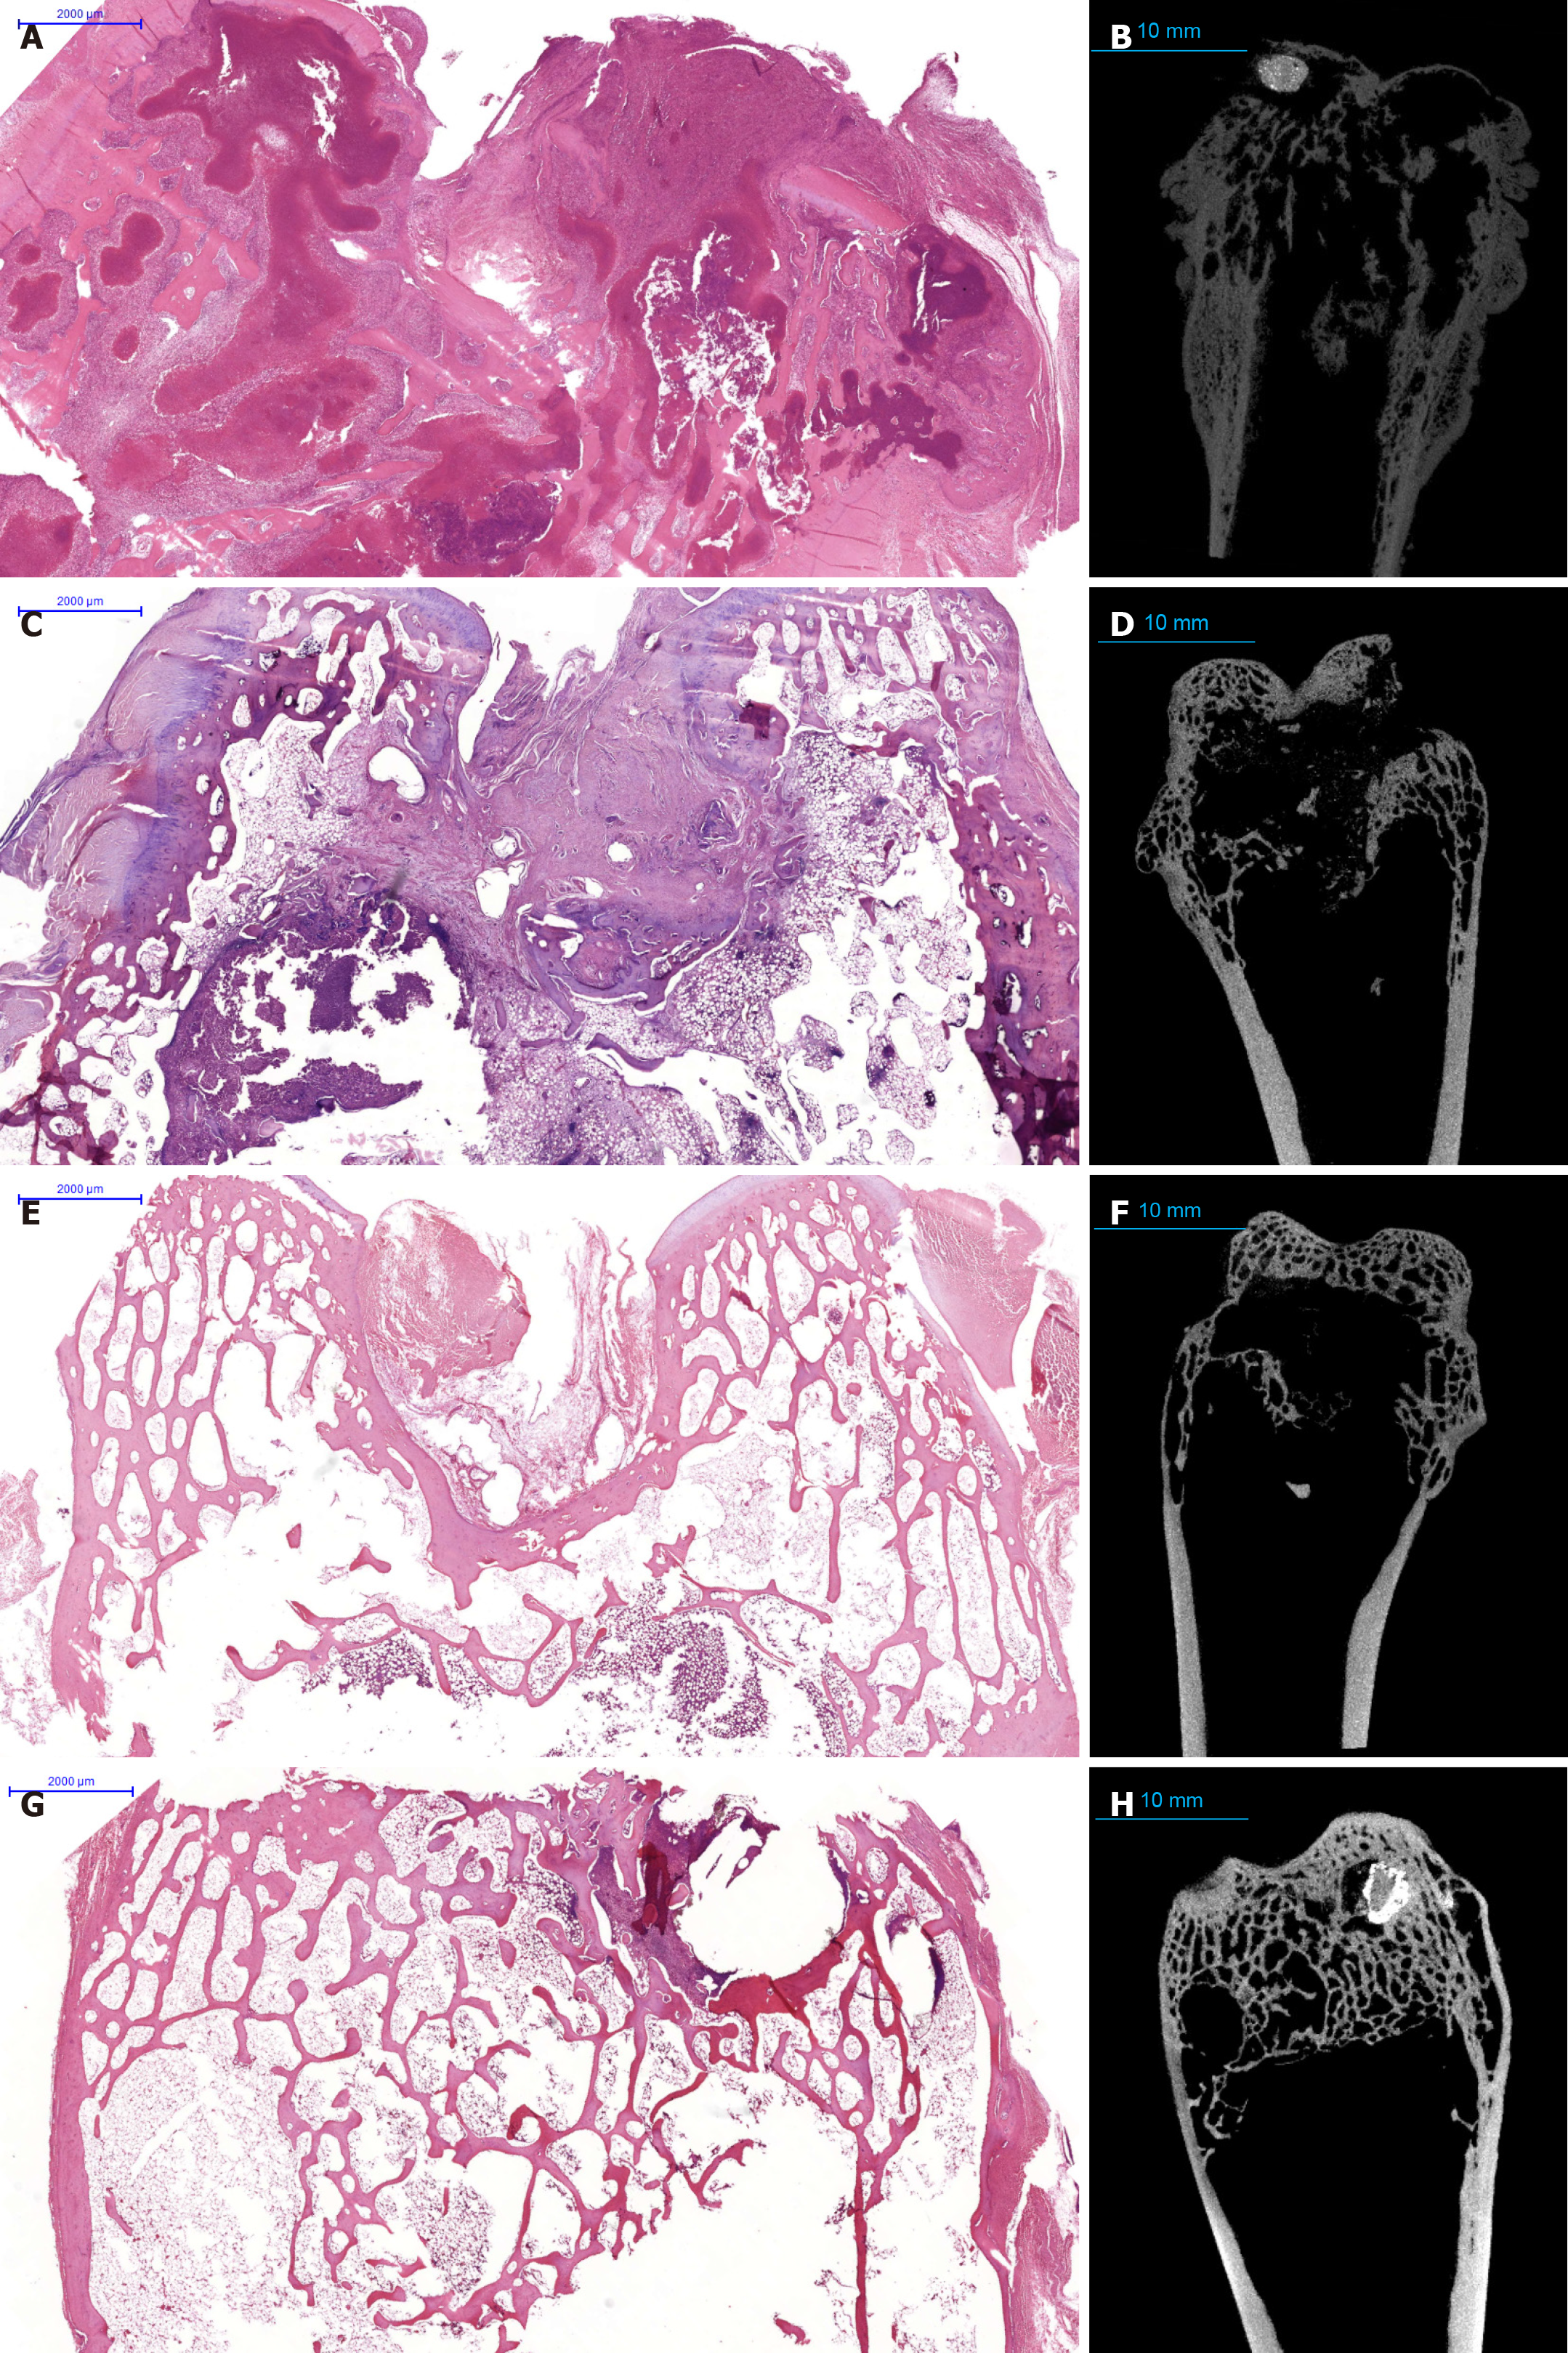

Figure 3 Pathological evolution of bone tuberculosis under different treatment regimens: A comparative histological and computed tomography analysis.

A and B: Group 1 (control) - infection was induced; no surgical or medical treatment was performed; autopsy at the 3-month control point. Scanned histologic section stained with hematoxylin and eosin, histological section showing specific inflammation occupying 405% of the specimen area, involving the metaphysis and diaphysis zones, including the articular surface (A); computed tomography (CT) cross-section of the corresponding macroscopic specimen of the epiphysis of the right femur, corresponding computed tomography image of the same distal femur region, the metaphyseal plate is not visualized due to severe inflammation (B); C and D: Group 2 - surgical or medical treatment + anti-tuberculous therapy-only, autopsy at 3 months control point. Scanned histologic section stained with hematoxylin and eosin, the area of specific displacement in the diaphysis contains necrosis with detritus in the center (C); CT cross-section of the corresponding macroscopic specimen of the epiphysis of the right femur (D); E and F: Group 2 - surgical or medical treatment + anti-tuberculous therapy-only, autopsy at 6 months control point. Scanned histologic section stained with hematoxylin and eosin, specific inflammatory infiltrates are determined in an area of no more than 1% of the epiphyseal zone, a single productive epithelioid cell granuloma surrounded by a ridge of lymphocytes is revealed (E); CT cross-section of the corresponding macroscopic specimen of the epiphysis of the right femur (F); G and H: Group 4 - surgical or medical treatment + pamidronate-only, autopsy at 6 months control point. Scanned histologic section stained with hematoxylin and eosin, the histoarchitecture of the epiphyseal zone is altered due to inflammation, the beam structure is partially restored, and the beams form a looped network in the epiphysis (G); CT cross-section of the corresponding macroscopic specimen of the epiphysis of the right femur (H). In the epiphysis zone, closer to the cortical bone, according to CT data, implant granules are visualized. Nonspecific inflammation, primarily characterized by lymphoplasmacytic infiltration, is also visible in this zone on histological preparations. Growing beams with active osteoblasts on the surface, full-blooded vessels, and isolated bone sequestra are found in this zone, a mature connective tissue capsule is present in some areas around the foci. Around the foci of inflammation, there is bone marrow remodeling, characterized by active mesenchyme and granulation tissue of varying maturity, with an increased number of full-blooded vessels. Stromal cords with lymphocytic infiltration extend from the inflammation zone; single multinucleated cells of the “foreign body” type are encountered, and diffuse single lymphocytic infiltration is found in the thickness of the bone marrow tissue.